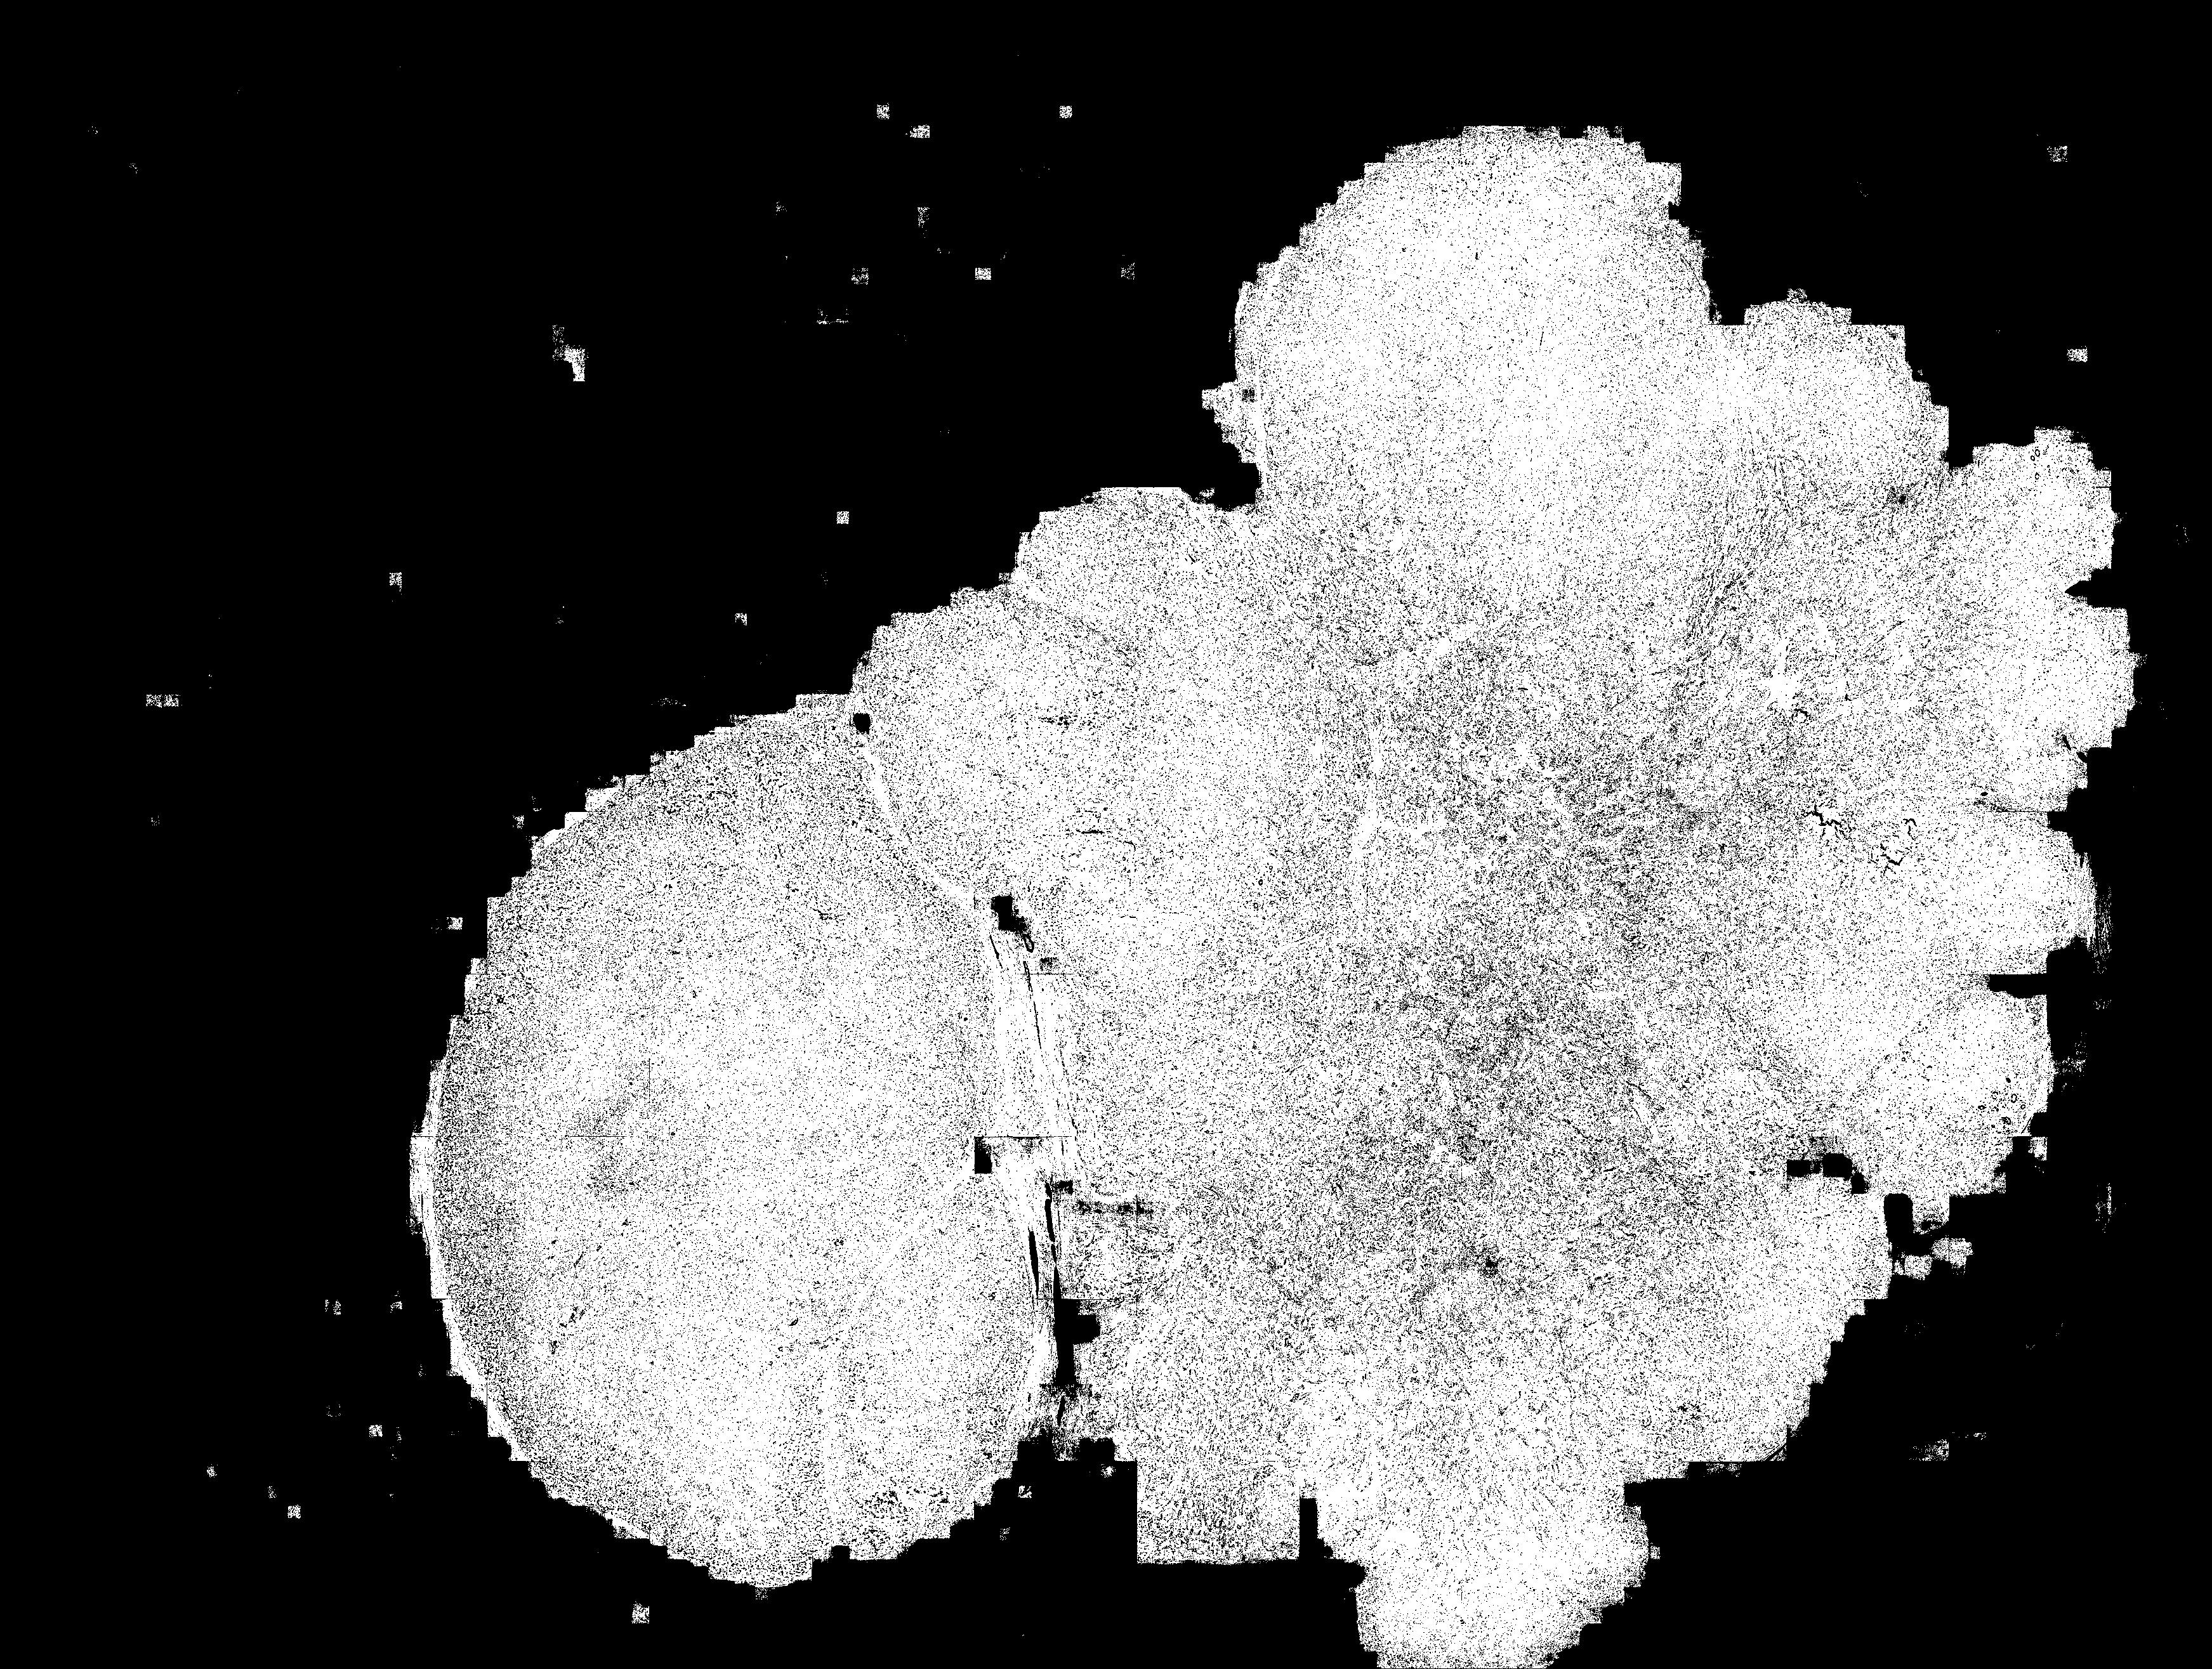

(a) Ground truth

(b) R18_U-Net (4096)

(c) TR-I

(d) HiTrans

4.2 Ablation study

The proposed hierarchical Tansformer encoder framework can learn global dependencies and bring muti-scale cues for the decoder during segmentation inference. In the ablation study, we removed the Transformer hierarchical add-on module, in order to evaluate the above argument, namely, that knowledge of global dependencies can enhance segmentation performance. Experiments without the add-on module using 512512 (Tab. 2, Exp. 1) and 40964096 (Tab. 2, Exp. 2) patches were conducted separately. Besides, an experiment using an architecture without Transformer encoder II was conducted (Tab. 2, Exp. 3). By comparing the experimental results, taking larger patches as input and using HiTrans to learn the global dependencies can lead to better segmentation results. Comparing with the results from add-on module dropped (Fig. 2, b) and Transformer encoder II dropped (Fig. 2, c) architecture, HiTrans can further improve the precision (Fig. 2, d) thanks to this regional and global dependency-aware architecture.